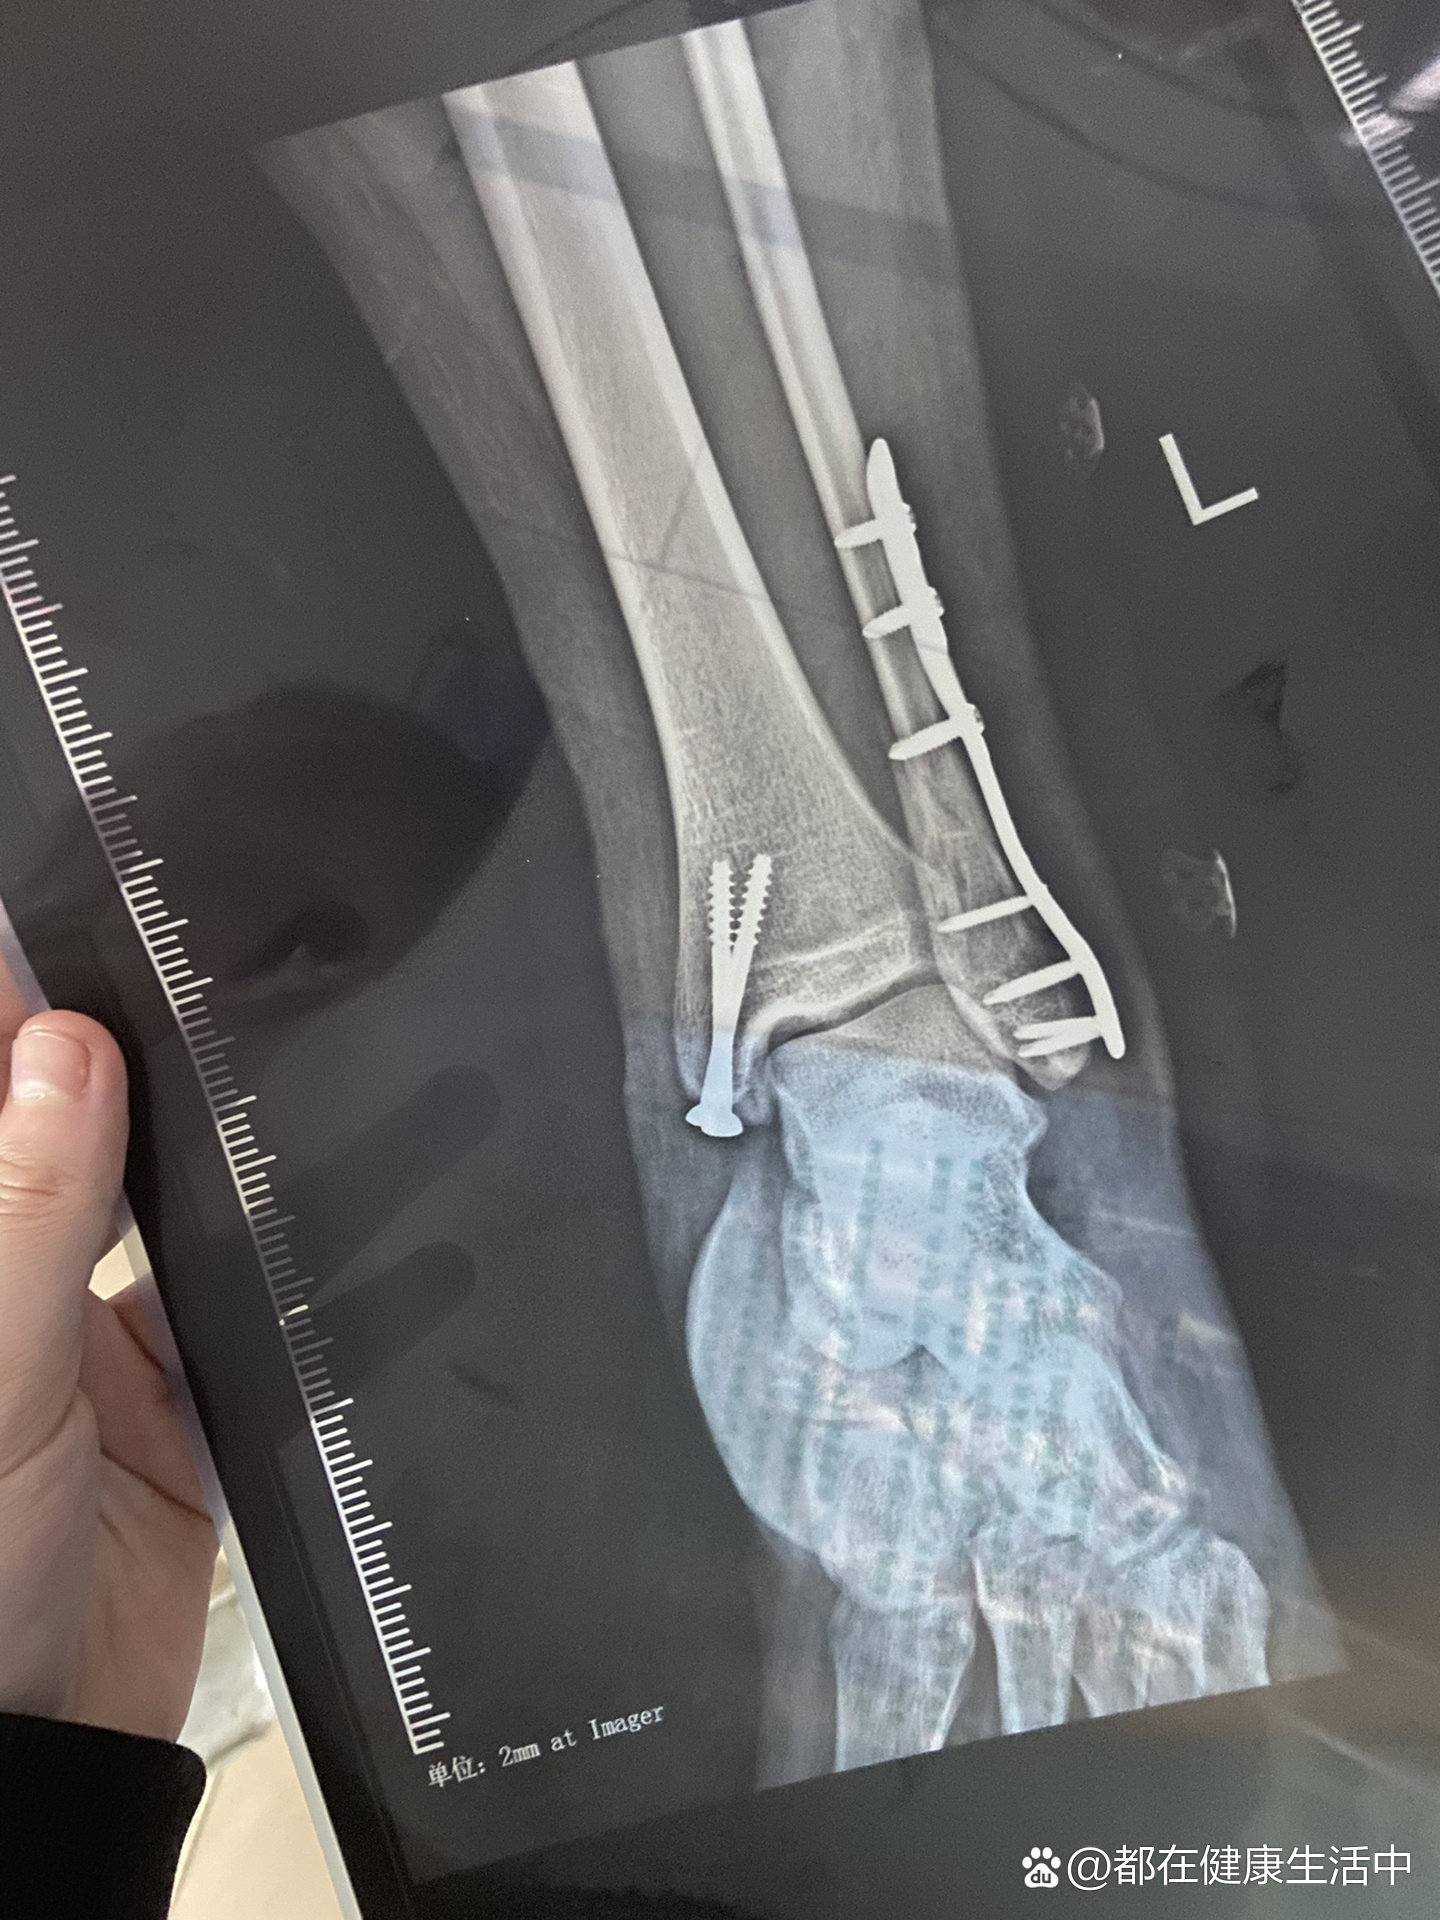

踝骨骨折手术后,通常需要812周可以下地具体情况如下功能锻炼阶段在手术后六周左右,骨折断端会通过大量的骨痂形成,使得稳定性得到显著提高此时,患者可以进行功能锻炼,以促进关节功能的恢复,但患肢不能负重正常负重阶段到812周时,骨折基本愈合通过拍摄X光片,可以发现骨折线变得模糊,甚至完全消。